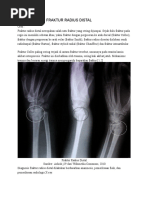

Fraktur radius distal adalah fraktur paling sering ditemukan di bagian gawat darurat; mereka menyumbangkan

sekitar 3% dari semua cedera ekstremitas atas dengan angka kejadian lebih dari 640.000 setiap tahun di Amerika

Serikat saja.

Cedera ini sering terjadi pada dua kelompok umur yang berbeda, dengan puncak pada usia 5 hingga 24 tahun.

kelompok pria yang beresiko terkena fraktur jenis ini adalah pria yang memiliki aktifitas fisik yang tinggi

seperti para atlet pada kelompok wanita fraktur biasanya terjadi akibat osteoporosis.

Data sensus di Amerika Serikat menunjukkan bahwa persentase fraktur colles terjadi pada usia 65 tahun keatas

akan meningkat dari 12% menjadi 19% dalam 25 tahun kedepan.